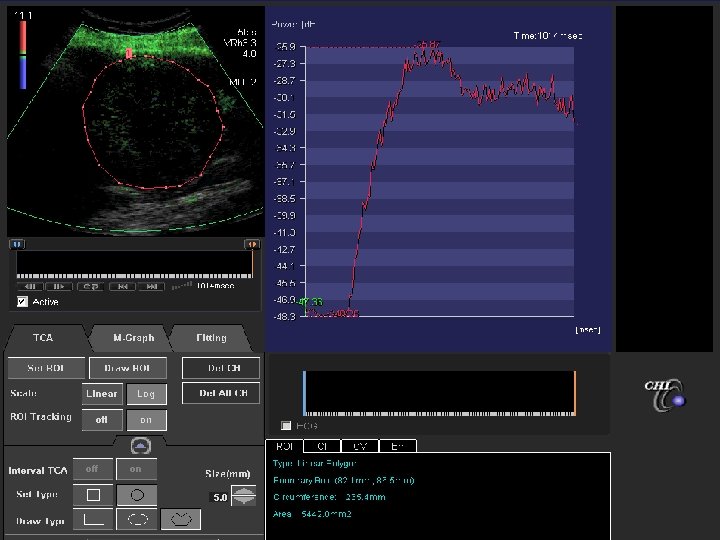

TARGETs Tumor Vascularization- US doppler can predict PFS Baseline Week 6